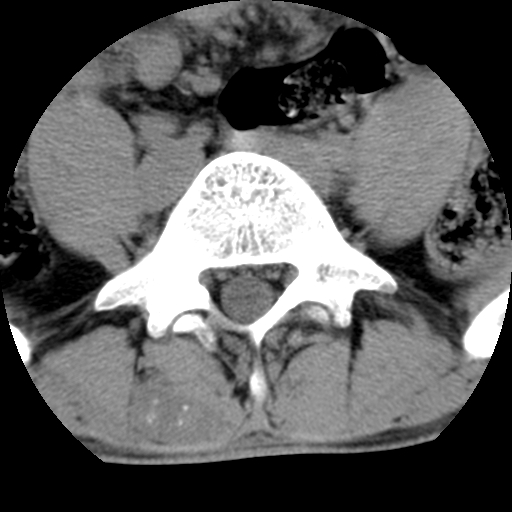

标题: CT16890:男,腰背痛.

男,腰背痛

本人诊断1tb2包虫,请会诊

1)右侧竖脊肌稍低密度肿块伴钙化(性质待定),不排除肿瘤可能;建议行进一步检查。2)腰椎间盘突出。

1.右侧竖脊肌软组织肿块伴团块状钙化,首先考虑血管瘤可能性大;建议行进一步检查;2。腰椎间盘突出。

软骨肉瘤可能性大